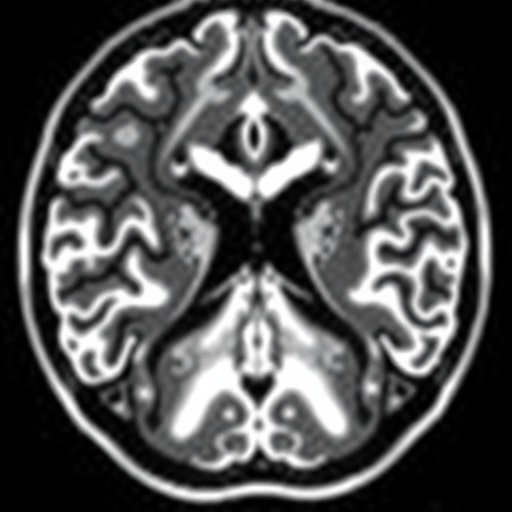

The concept of nigrosome integrity has emerged as a promising neuroanatomical biomarker. Nigrosomes, particularly nigrosome-1, are clusters of dopaminergic neurons whose degeneration correlates with the severity of Parkinson’s pathology. Advanced MRI techniques have enabled visualization of these nigrosomes in vivo, creating an opportunity for non-invasive assessment before surgery. The research team sought to critically assess whether the intactness of nigrosomes, observable prior to DBS, could serve as a reliable predictor of motor outcome improvements.

Employing cutting-edge imaging combined with meticulous clinical evaluations, the scientists analyzed preoperative nigrosome status in a cohort of PD patients scheduled for DBS. This comprehensive approach extended to post-surgical monitoring of motor function using standardized scales such as the Unified Parkinson’s Disease Rating Scale (UPDRS). Contrary to prevailing expectations, their data revealed that preoperative nigrosome integrity exhibited limited predictive power regarding the motor benefits patients experienced following DBS.